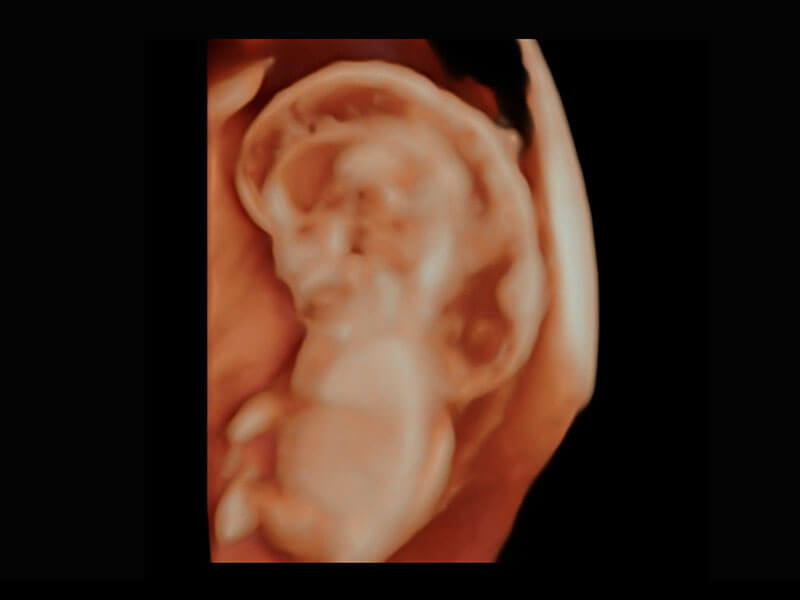

高分辨率容积成像-早孕胎儿

胎儿体循环

光影成像-孕囊